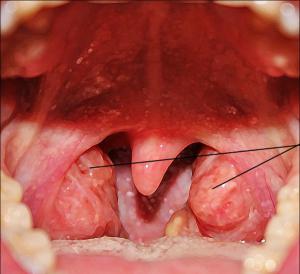

Воспаленные миндалины имеют разную структуру. Например, небные (или гланды) имеют лакуны и фолликулы, которые пронизывают миндалины насквозь. В здоровом состоянии эти лакуны и фолликулы вырабатывают достаточное количество лимфоцитов, чтобы человек не заболел. Но, если заражение произошло, возможна фолликулярная или лакунарная ангина.

Так или иначе, нельзя недооценивать воспаление миндалин, возможны осложнения. Фото ярко иллюстрируют этот процесс.